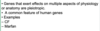

Identify factors that may affect the disease expressing genes and explain their contribution to human diseases utilizing specific examples.

- What does the image describe? The answer choices are below.

- Locus Heterogeneity

- Mosaicism

- Pleiotropy

- Penetrance - Incomplete

- Penetrance - Age-dependent

- Variable expression

- New mutations (de novo)

Pleiotropy

Identify factors that may affect the disease expressing genes and explain their contribution to human diseases utilizing specific examples.

- What does the image describe? The answer choices are below.

- Locus Heterogeneity

- Mosaicism

- Pleiotropy

- Penetrance - Incomplete

- Penetrance - Age-dependent

- Variable expression

- New mutations (de novo)

New mutations (de novo)